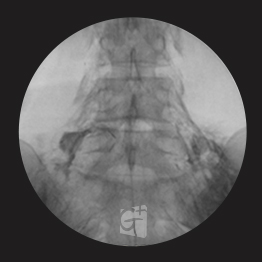

경추 신경성형술

-

경추 좌측 2번 신경절

경막외 카테터 삽입 -

척추관 안쪽으로 진입하여 약물 주입

-

원인부위 염증 제거 및 유착 박리

-

유착박리로 추간공 확보 신경 압박 감소

-

척추관에서 약물이 퍼져나오는 모습

-

목 신경 전체를 효과적으로 치료